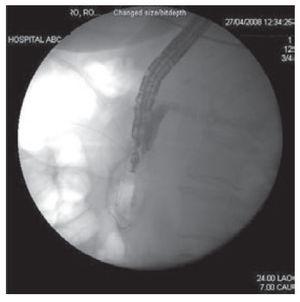

The echoendsocope was placed in the duodenum and was oriented to visualize the extreahepatic biliar system. Color Doppler was used to identify regional vasculature. CBD was punctured under continuous endosonographic guidance using a 22- Gauge needle (Echo tip Ultra; Cook Medical Inc. Winston-Salem NC). To confirm successful biliary access, bile was aspirated through the needle followed by biliary opacification instilling contrast under fluoroscopy. (Figure 2). A 0.018 inch guide wire (Glidewire; Microinvasive Endoscopy, Boston Scientific Corp) was inserted through the EUS needle and advanced in an antegrade fashion, into the duodenum across the papillary orifice.

Figure 2. Fluoroscopic image showing opacification of the common bile duct after gaining access into the common bile duct under continuous endosonographic guidance using a 22-Gauge needle.